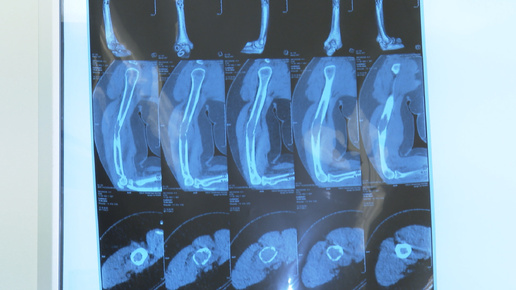

Неделя профилактики онкозаболеваний проходит в Иркутской области